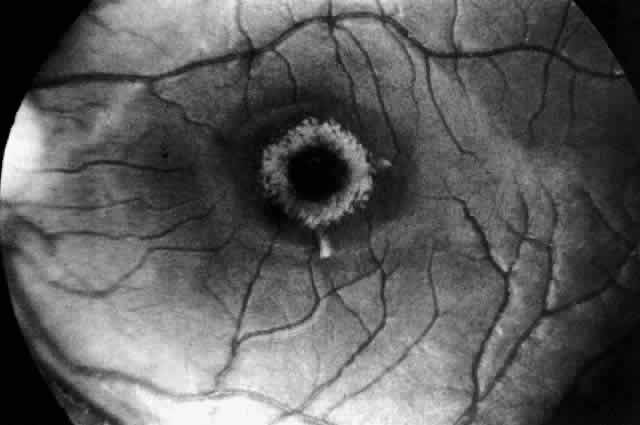

OCULAR MANIFESTATIONS. The retinal changes in Farber's disease are subtle and easily overlooked. The fundi of one 8-month-old patient had been examined several times following the onset of the disease at age 2 weeks and considered to be normal. Cogan and colleagues95 subsequently observed and reported a diffuse grayish opacification of the retina about the fovea, producing a mild cherry-red spot (Fig. 9). The parafoveal opacity differed from that seen in Tay-Sachs disease in that the opacity was pale gray instead of white and it was accompanied by little, if any, pallor of the optic disc. Shortly before death at age 11 months there was a suggestion of a peppery pigmentation of the entire retina and some abnormal pigmentation in the macula. The retinal vessels showed no abnormality. Visual function, as judged by the patient's attentiveness, retention of the optokinetic response, and absence of nystagmus, was normal.

Fig. 9. Fundus of patient with Farber"s disease at age 8 months. Macula shows abnormal grayness with suggestion of cherry-red center. Retinal vessels are normal, and color of disc is normal. (Cogan DG, Kuwabara T, Moser H et al: Retinopathy in a case of Farber"s lipogranulomatosis. Arch Ophthalmol 74:752, 1966. Copyright © 1966, American Medical Association)